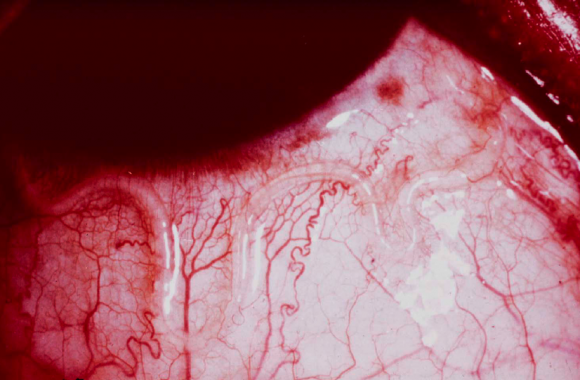

≪MOVIE≫ Solitary Subconjunctival Moving Parasite- Dirofilaria repens.